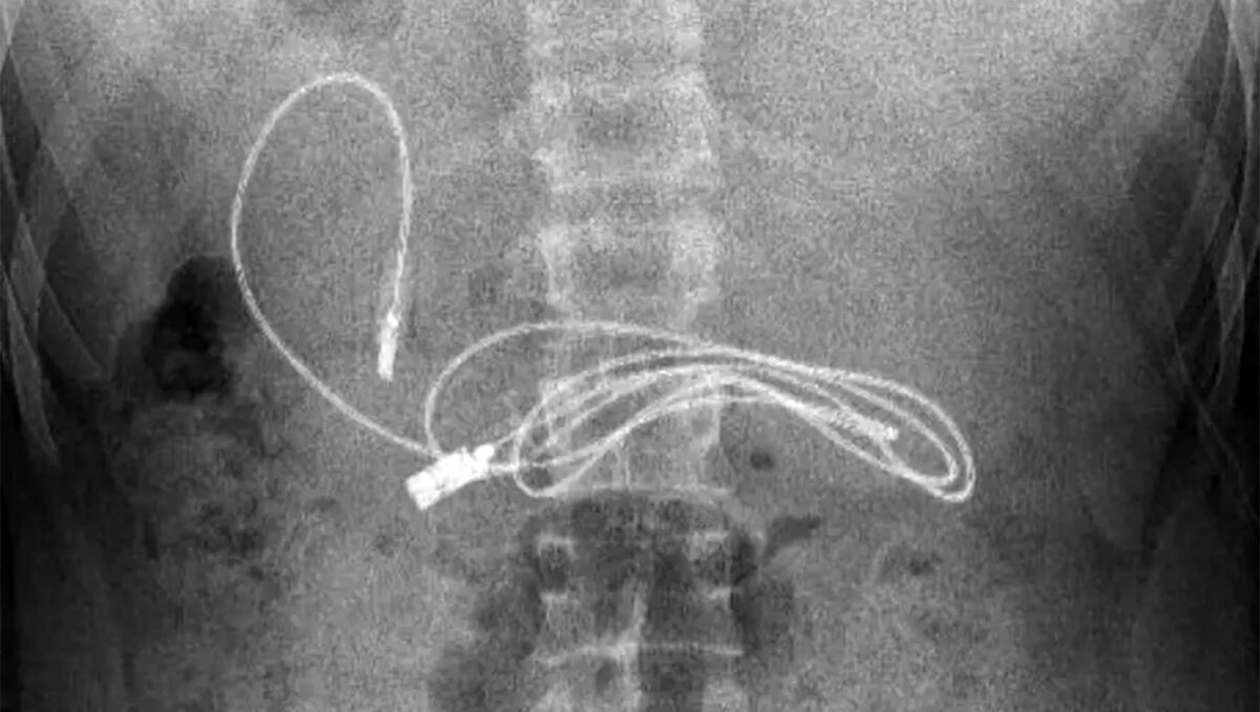

Când medicul gastroenterolog i-a văzut radiografia a stabilit clar că adolescentul a înghițit un cablu USB pentru telefon și căști. Pentru a reuși să-l extragă, i-a făcut o endoscopie și o mică incizie. Mai mult de atât, cablul era înconjurat de păr care, la fel, nu se știe cum a ajuns acolo. Tânărul nu a vrut să spună cum a reușit să își introducă gadgetul în stomac.

Cea mai grea parte în procesul de îndepărtare al gadgetului din stomac a fost că era atât de lung, încât o parte reușise să treacă în intestinul subțire, după cum a dezvăluit medicul.

„În mod evident, ne-a fost greu să scoatem cablul, deoarece un capăt al cablului a trecut în intestinul subțire”, a spus gastroenterologul pediatru Yasar Dogan.